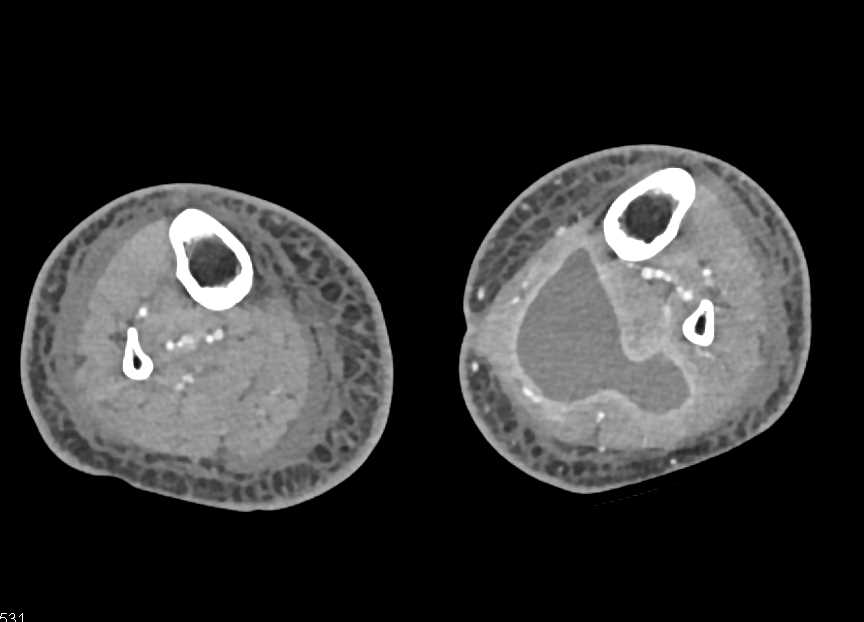

Left Distal Femur Fracture in Patient with Hardware